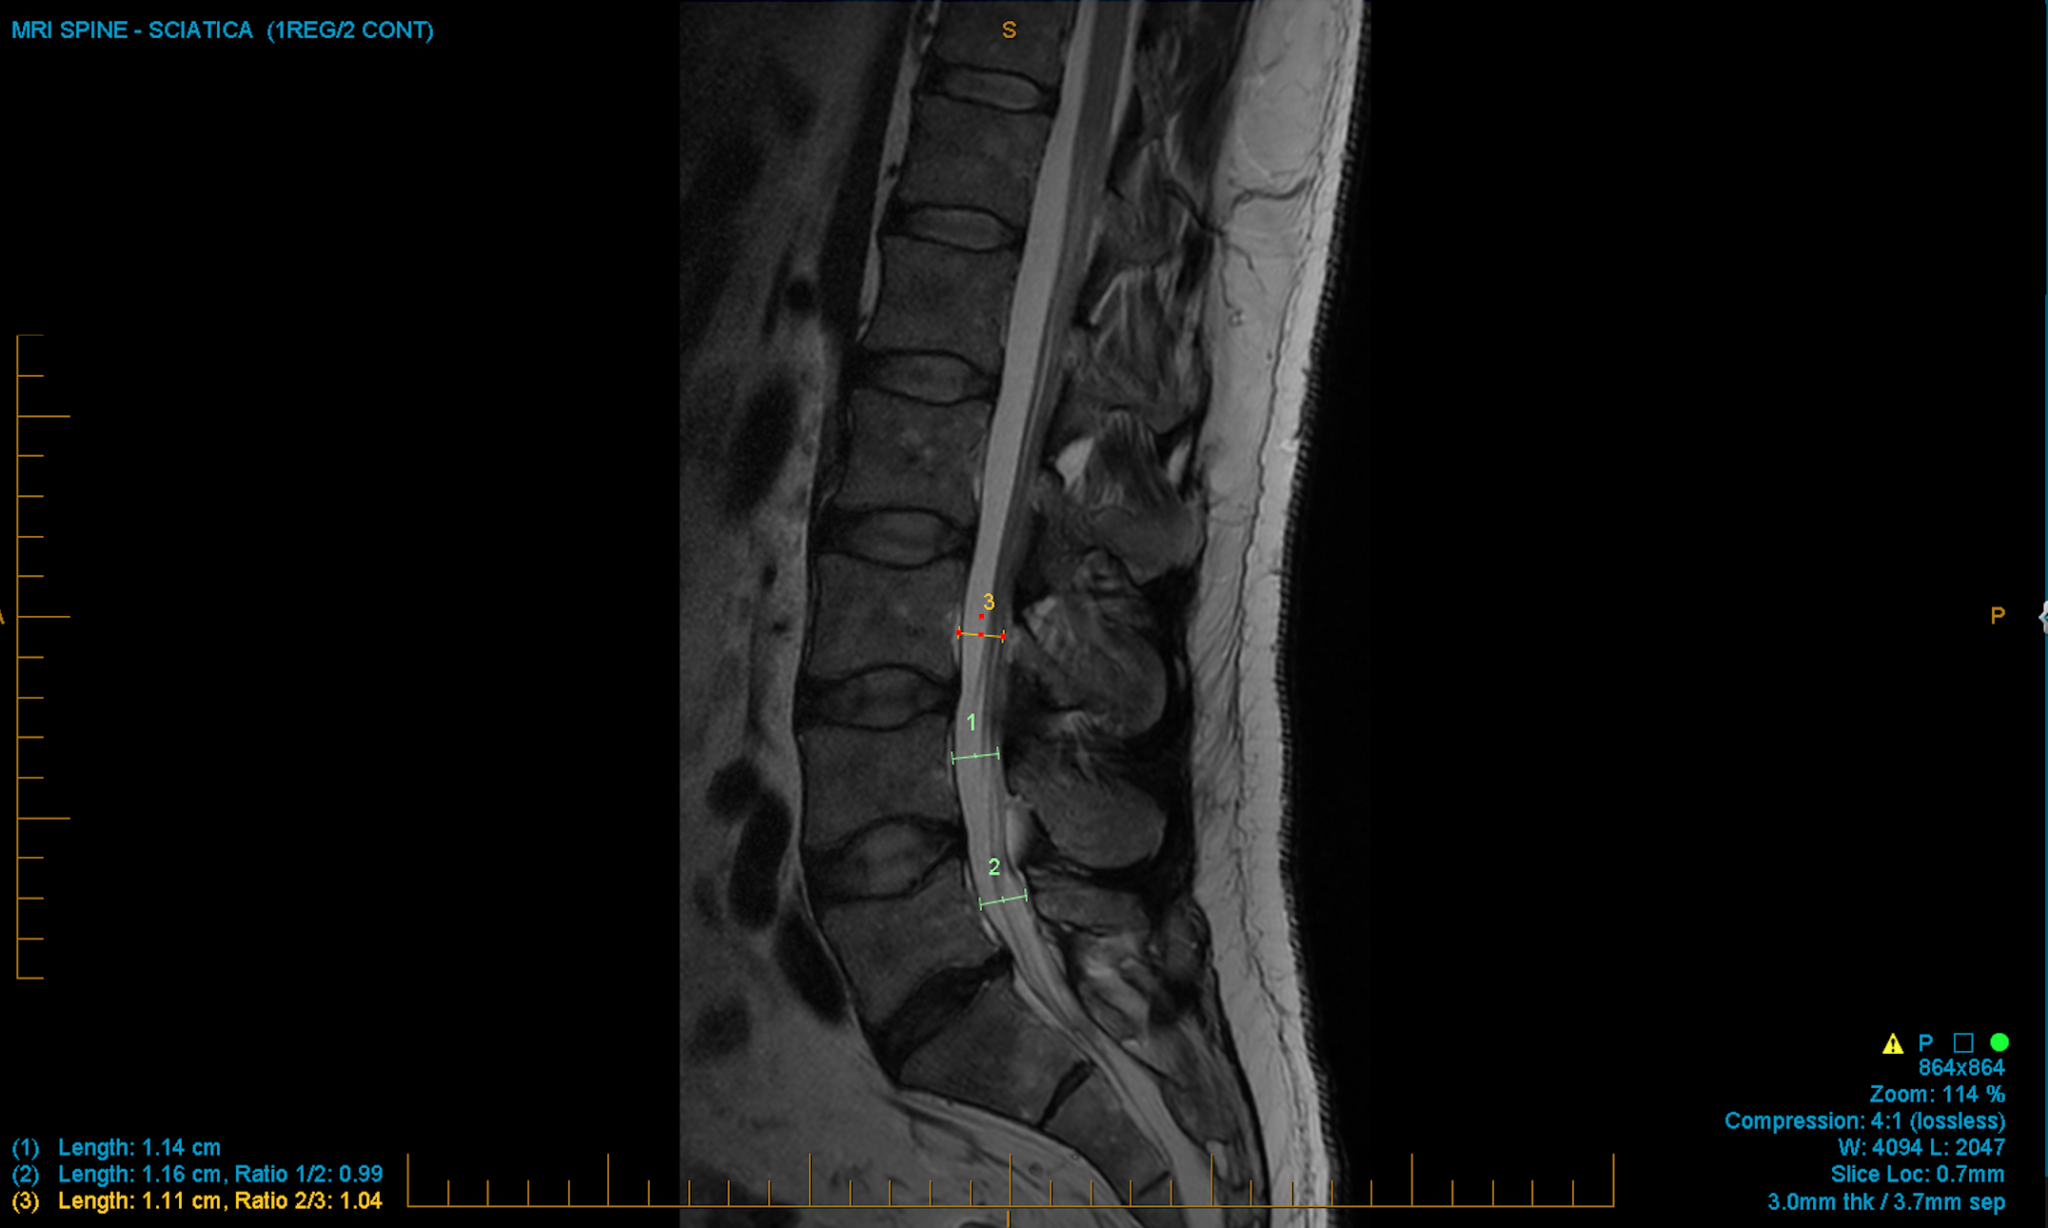

a. Xray of the lumbar spine revealed narrowing of intervertebral space